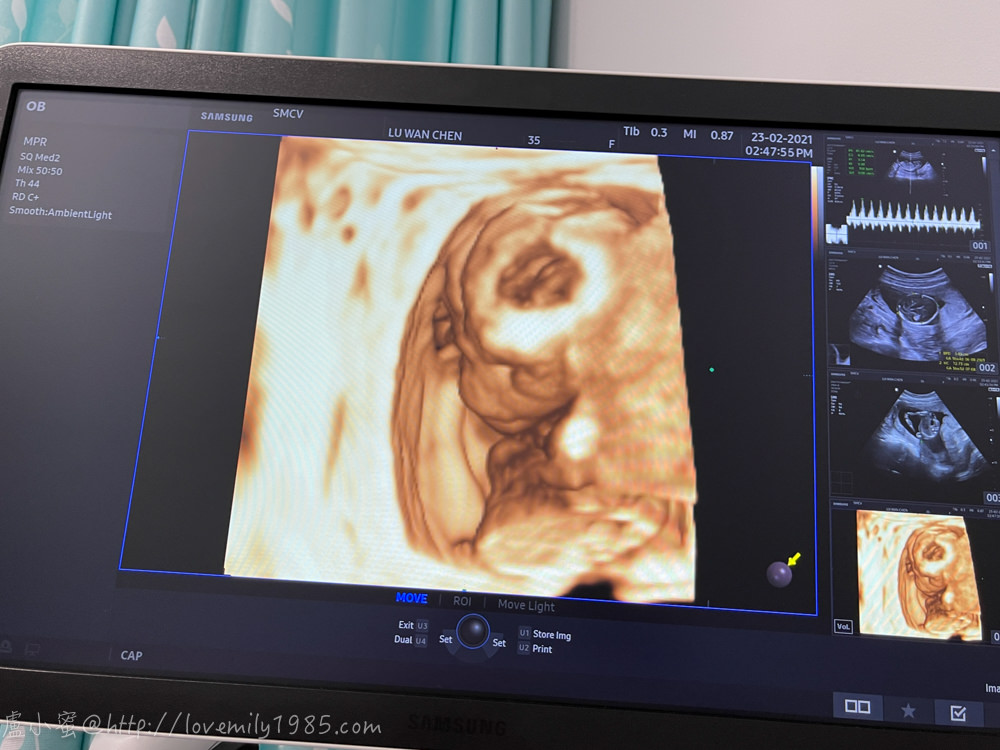

原本照完剛剛的超音波就結束了,但我突然想到之前在台灣產檢都有照那種立體的

於是我就順口問問這邊有照這種的嗎?還是要去別的地方照?沒想到就獲得意外的收穫!

醫生說其實同一台機器可以照,只是現在照出來不會很漂亮喔,要等大一點才會比較有肉

我說「我知道,我前兩胎在台灣產檢都有照,寶寶就很像骷髏頭」

醫生聽了笑出來,她說因為這邊媽媽好像有些人比較不習慣看到寶寶”不像人”的樣子

所以通常週數比較小時不太會主動照立體的超音波

於是我本來起身了,又躺回去~再照一次!

果然,現在照起來超像“河童”的,你們看得出來哪裡是鼻子嘴巴嗎?哈哈